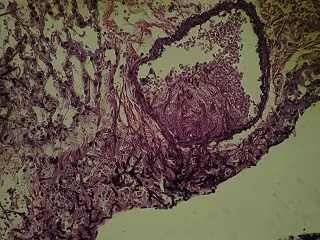

Állatkísérletek végzése tüdőaszpergillózis egérmodellen.